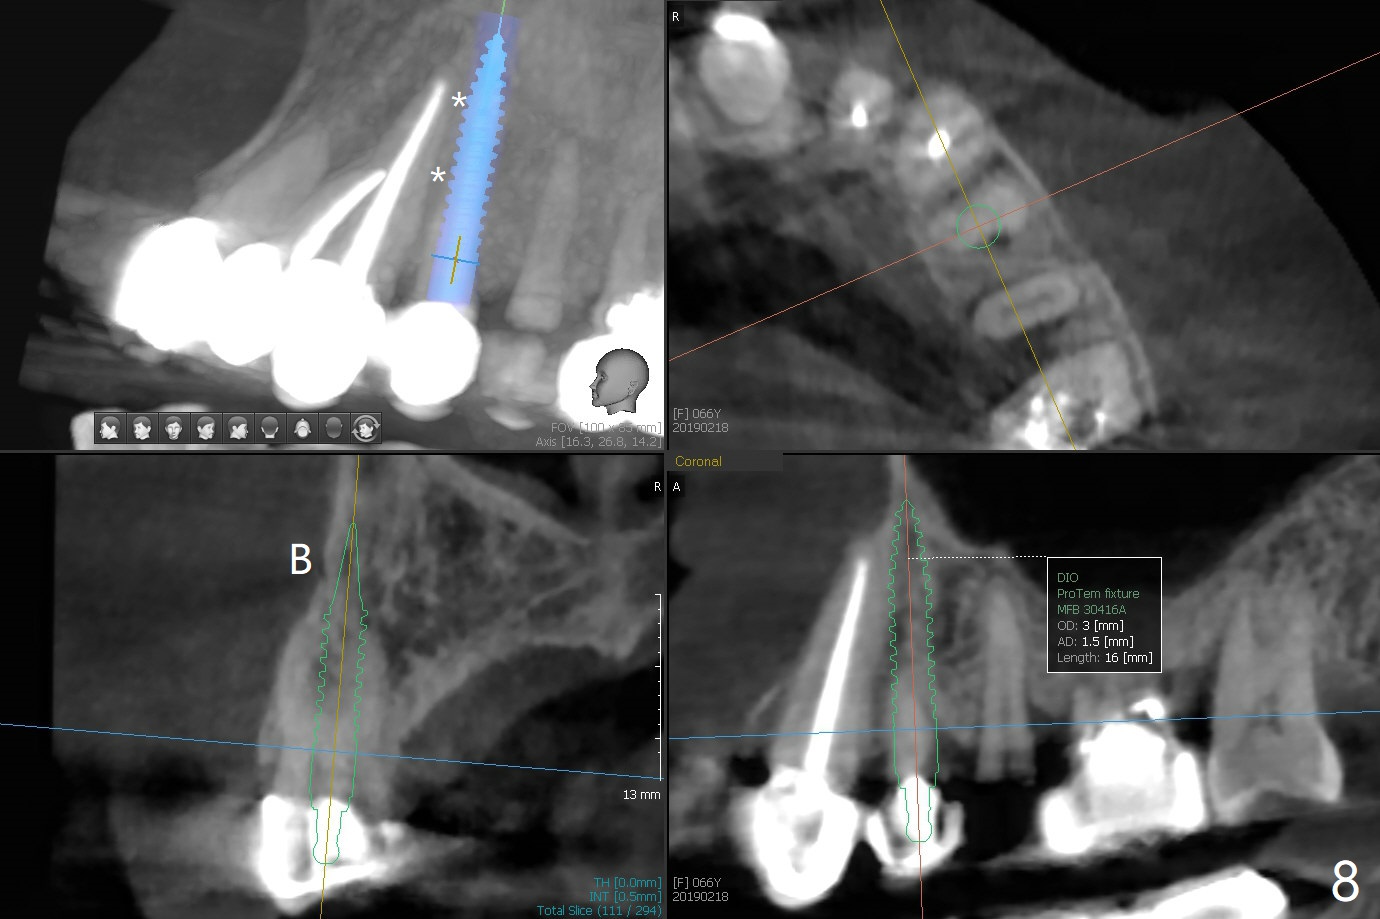

68岁女左上4颊侧瘘道(图一:*),与根尖颊侧骨板缺失相通,其实腭侧根尖周围病变更大(也与颊侧窝相通),术中没有注意腭侧根接近3(图二:P),稀里糊涂的基本顺着腭侧根(颊侧)走向钻洞(图四,与图三理想方向对比),突然记起术前设计钻洞必须在腭侧牙槽窝远中颊侧,在远中建立新洞眼(图五),之后无法再次建立新洞眼,只好利用同一个侧面切割钻头将钻洞往远中移位,同样效果不佳(图六),最后只好放弃,放置粘性骨粉(图七:*),覆盖PRF膜,6个月胶原膜,PGA缝线,牙周胶水。术后重新分析表明顺着腭侧牙槽窝种植与尖牙还是有分离(图八,九:*),因为牙槽窝是斜型的(图十:黑色),不过离颊侧骨板也接近(图八:B)。所以钻洞必须斜型针对远中骨壁,表浅些(图十一:红色箭头);一旦进入骨板,改变角度(图十二:红色箭头),适当矫枉过正,随着植体增大,钻洞会往近中偏移(白色箭头)。最好植体方向理想(图十三)。不过植骨后钻洞偏移可能性比较少。缝线和牙周胶水似乎是一个稳妥固定胶原膜方法。术后病人抱怨水肿严重,术后八天颊侧根尖隆起是由于骨粉推出骨板之外(图十五,十六:*),上颌窦底板无意穿孔(^)伴有上颌窦膜(M)增厚,与术前对比(图十七:上颌窦窦腔清晰)。术后一个月6个月吸收膜不见了,大多数缝线已经脱落,最后两根缝线撤除后,牙槽窝开口已经关闭,好像主要成分是骨粉(图十八)。术后5个月牙槽嵴宽,角化龈也宽,好像可以植入4x11.5毫米植体(图十九)。